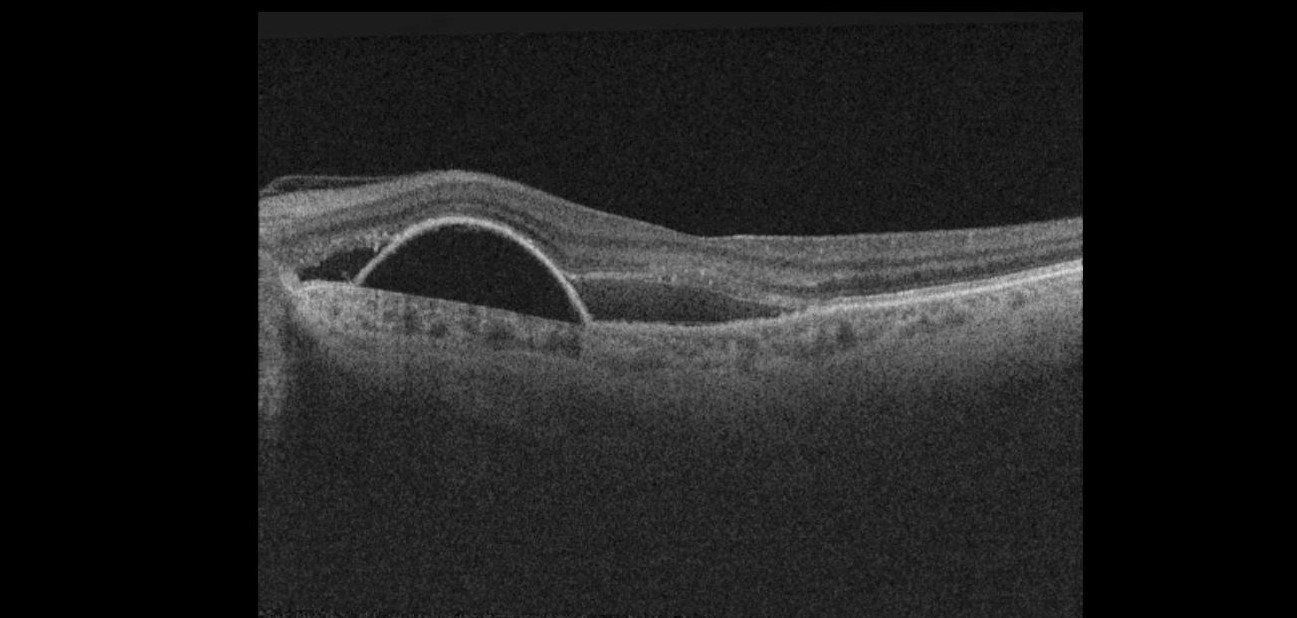

Full thickness macular hole -This is a defect that affects all the layers at the macula. One cause of this is when the jelly at the back of the eye pulls away, but ‘does not let go’ causing the retina to tear and leaves a hole.